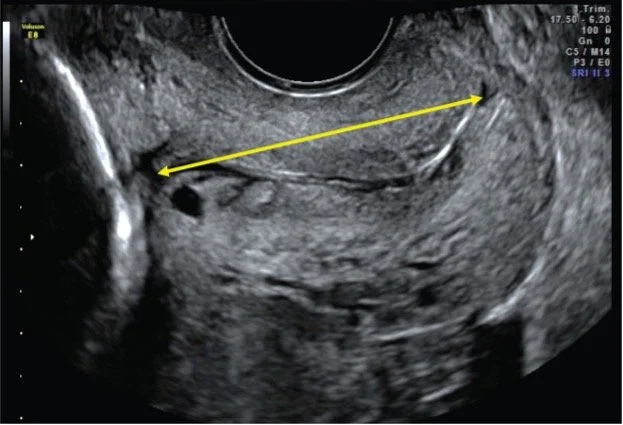

Created in close collaboration with women undergoing cervical scans, writer Hazel Gould and Professor Anna David, the work draws on 16 hours of research and interviews with patients and staff in preterm birth clinics at the Elizabeth Garrett Anderson Wing, University College Hospital London. The aria is sung by a fictional patient. It explores experiences of internal vaginal ultrasound scans for the purpose of cervical measurement and assessment of preterm birth risk.

Image: A cervical scan measurement courtesy of the artist and Birth Rites Collection